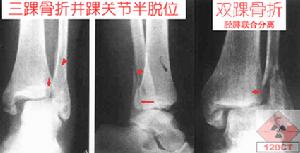

踝部骨折(一)外翻骨折受傷時,踝部極度外翻,或重物壓於外踝,使踝關節極度外翻。因暴力強度的不同,可引起不同程度的損傷。輕者為內踝撕脫骨折,稱單踝(或Ⅰ度)骨折,骨折線呈橫形。若暴力持續,距骨將撞擊外踝,造成外踝的斜形骨折或下脛腓韌帶撕裂,稱兩踝(或Ⅱ度)骨折。當下脛腓韌帶撕斷後,腓骨可在更高的位置骨折,距骨同時向外側脫位。若同時合併外鏇暴力,可引起腓骨螺鏇形骨折。

(二)內翻骨折受傷時,踝部極度內翻,可因不同強度的暴力引起不同程度的損傷。輕者可引起外側副韌帶損傷伴有腓骨尖撕脫或外踝橫形骨折,稱單踝(或Ⅰ)骨折。若暴力持續,距骨將撞擊內踝,引起內踝斜形骨折,稱兩踝(或Ⅱ度)骨折,有時也可引起下脛腓韌帶和距骨跟腓韌帶撕裂,使踝關節不穩定,嚴重暴力可引起雙踝骨折和距骨向內半脫位在上述暴力作用的同時,若踝關節處於內收跖屈位,則暴力可同時向後,引起距骨向後移位,撞擊後踝,引起後踝骨折,稱三踝(或Ⅲ度)骨折。若受傷時,踝關節處於背屈位,可引起脛骨前唇骨折。